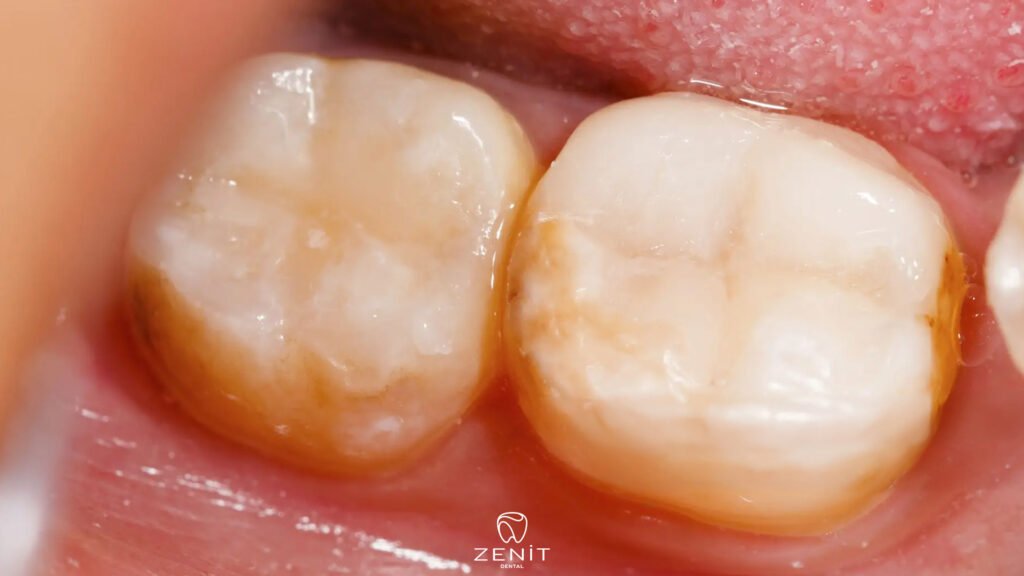

One of the most common causes is poor oral hygiene. When teeth are not cleaned properly and regularly, bacteria start to accumulate especially around the edges of the filling. These bacteria produce acid over time and slowly weaken the tooth structure without being noticed. Most of the time, the person does not feel it early because the process is silent.

Another important reason is the tiny gaps that can form between the filling and the tooth over time. These gaps may be too small to see, but they create a perfect space for bacteria. When food particles and microorganisms settle in these areas, decay usually begins under or around the filling. This is why people sometimes hear that “there is decay under the filling,” which is exactly how it happens.

In addition, the natural wear of fillings over the years is another important factor. No filling material lasts forever in its original condition. It can wear down, develop small cracks, or lose its perfect seal with the tooth. On top of that, habits like frequent sugar consumption, acidic foods, and teeth grinding can also weaken both the tooth and the filling. When all these factors come together, it becomes much easier to understand why a filled tooth can decay again.